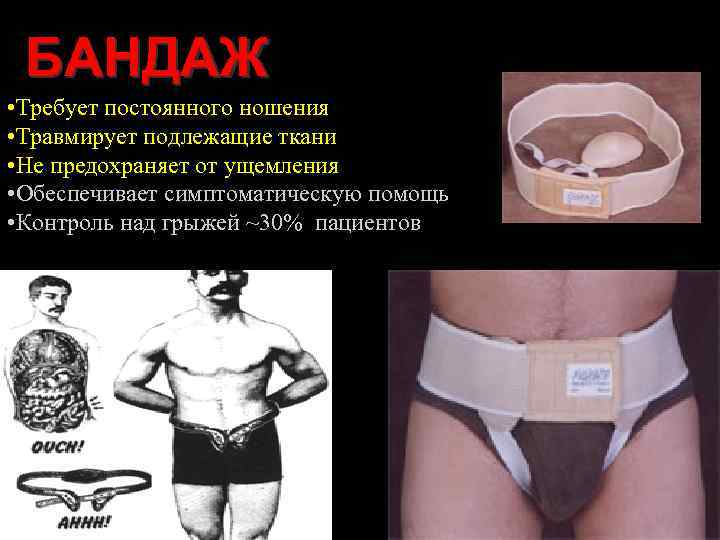

БАНДАЖ • Требует постоянного ношения • Травмирует подлежащие ткани • Не предохраняет от ущемления • Обеспечивает симптоматическую помощь • Контроль над грыжей ~30% пациентов